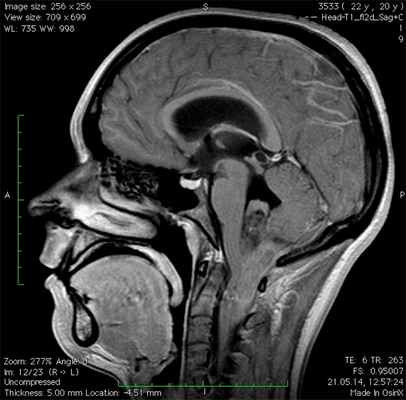

Большинство эпендимом головного мозга (60%) локализуются в задней черепной ямке (инфратенториально), возникая в области дна 4го желудочка, особенно у детей 7. В остальных случаях (40%) локализуясь супратенториально составляют вплоть до половины интрапаренхиматозных случаев [7].

Эпендимомы задней черепной ямки обладая пластичностью распространяются через отверстия Лушка и Мажанди. Данный признак может быть визуализировать при КТ и МРТ.

- Супратенториальная область составляет верхние две трети головного мозга. Он включает в себя головной мозг, а также боковые и третий желудочки.

- Инфратенториальная область составляет нижнюю треть головного мозга. Он включает ствол головного мозга, мозжечок и четвертый желудочек.

Обычно обнаруживают объемное образование в дне IV желудочка, часто с окклюзионной гидроцефалией.

Рентгенологически может быть трудно отличить от медуллобластомы, могут помочь следующие признаки:

2. Медуллобластомы обычно возникают из крыши IV желудочка (из его вершины, фастигиума), который покрывает опухоль («симптом банана»), эпендимомы имеют тенденцию врастать в IV желудочек со дна

Эпендимома зачастую локализуется в четвертом желудочке головного мозга, откуда склонна прорастать в область мозжечка и ствол головного мозга. Такой рост новообразования называется инфратенториальным.

Эпендимомы — опухоли, возникающие из эпендимальных клеток, могут возникать в головном или спинном мозге.Когда эти опухоли возникают в головном мозге, они обычно описываются как возникающие либо в супратенториальной, либо в инфратенториальной области мозга.